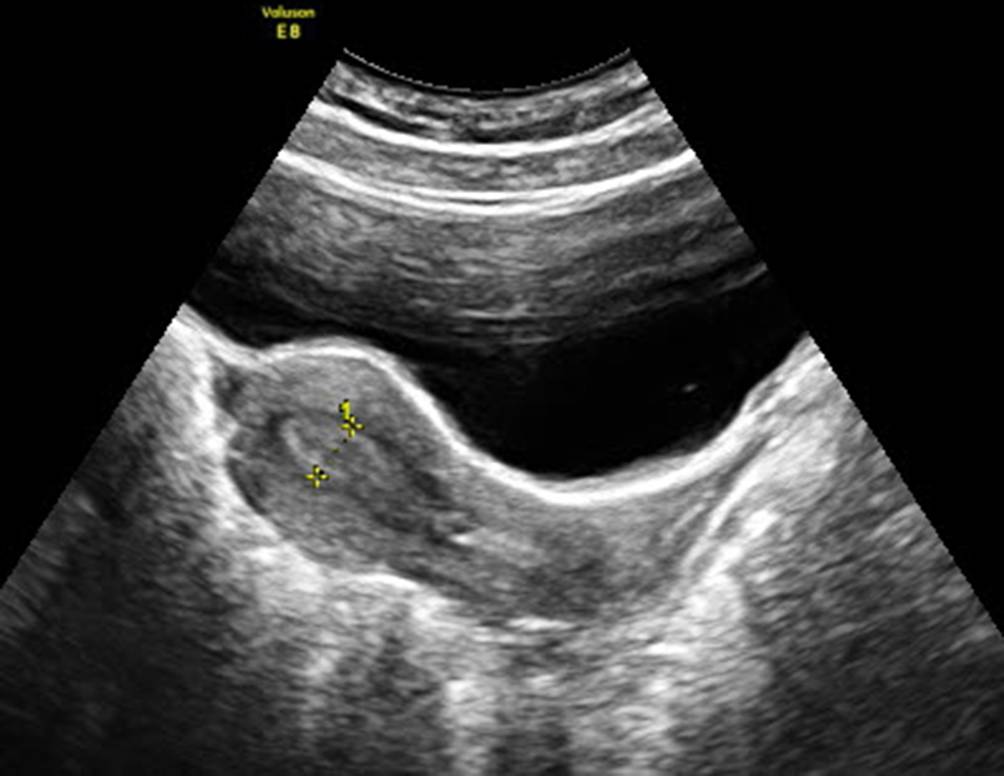

Das ovarielle Hyperstimulationssyndrom (OHSS) ist dank der heutigen Stimulationsprotokolle selten geworden, daher ist es sehr wahrscheinlich, dass es – wenn es doch einmal auftritt – ÄrztInnen einer Notaufnahme noch nie zuvor gesehen haben. Markant vergrößerte Ovarien und eine Flüssigkeitsansammlung in der Bauchhöhle sind ein wesentliches Charakteristikum des OHSS (Abb. 13). Der mit der Vaginalsonde einsehbare Bereich ermöglicht keine verlässliche Einschätzung des Volumens der freien Flüssigkeit. Daher muss fast zwangsläufig die Abdominalsonde verwendet werden. Wichtig ist eine standardisierte und gut dokumentierte Messung (Abb. 14). Den Schallkopf im rechten Oberbauch so einstellen, dass man den Unterrand der Leber sieht (Abb. 15): Eine Serie von Messungen an dieser Stelle gibt die verlässlichste Information, ob ein OHSS-Aszites über Tage zunimmt, konstant bleibt oder abnimmt [4]. Es besteht die Möglichkeit, die Menge der freien Flüssigkeit in den vier Quadranten des Abdomens zu addieren und – ähnlich dem Amniotic-fluid-Index im Schwangerenultraschall – aus den einzelnen Messstrecken einen Aszitesindex zu dokumentieren [5]. Nützlich ist es auch, sich von Kollegen, die z. B. als Gastroenterologen täglich im Oberbauch ultraschallen, einige Tipps geben zu lassen und deren Leitlinien zur Asziteskontrolle und Punktion zu beachten [6].

Abb. 13

Überstimuliertes Ovar mit Maximallänge 8 cm von abdominal